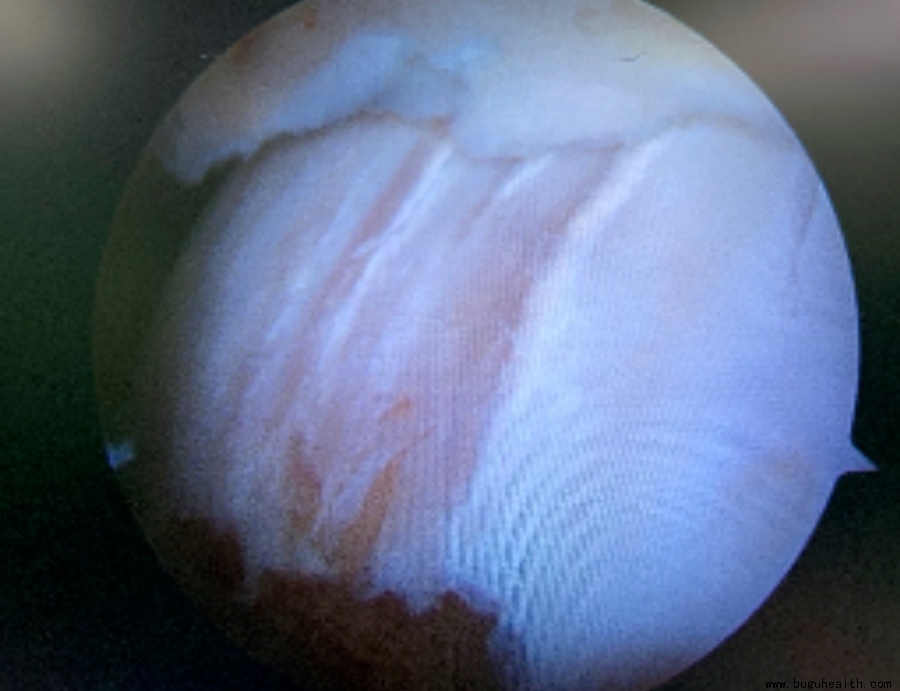

在一些长期踝关节不稳定的患者中,距骨软骨表面常常会出现下面的软骨磨损,引起踝关节的疼痛。

短期来看,这并没有太大的问题,因为在距骨表面有一层光滑的软骨,可以暂时缓冲这种压力,但是,随着时间的延长,距骨软骨就会出现龟裂、剥脱、磨损。